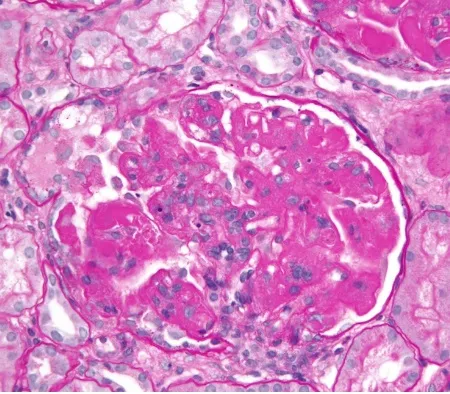

La discrepancia entre la remisión clínica y la histopatología es evidente, ya que con frecuencia un paciente puede presentar actividad histológica de la enfermedad incluso en ausencia de hematuria y proteinuria. Además, la proteinuria puede ser secundaria a lesiones crónicas.

En el estudio vinculado ([enlace](https://doi.org/10.1093/rheumatology/keaa129)), el enfoque de suspender los IS con orientación mediante biopsia renal resultó prometedor. Se observó una tasa de recurrencia de brotes renales en solo el 9% de los pacientes, lo cual es significativamente menor en comparación con las tasas previamente descritas por el mismo grupo.

* La repetición de la biopsia renal puede ser una herramienta valiosa para evitar la reducción de los IS en pacientes con actividad subclínica de la nefritis lúpica, evitando desescaladas inadecuadas.